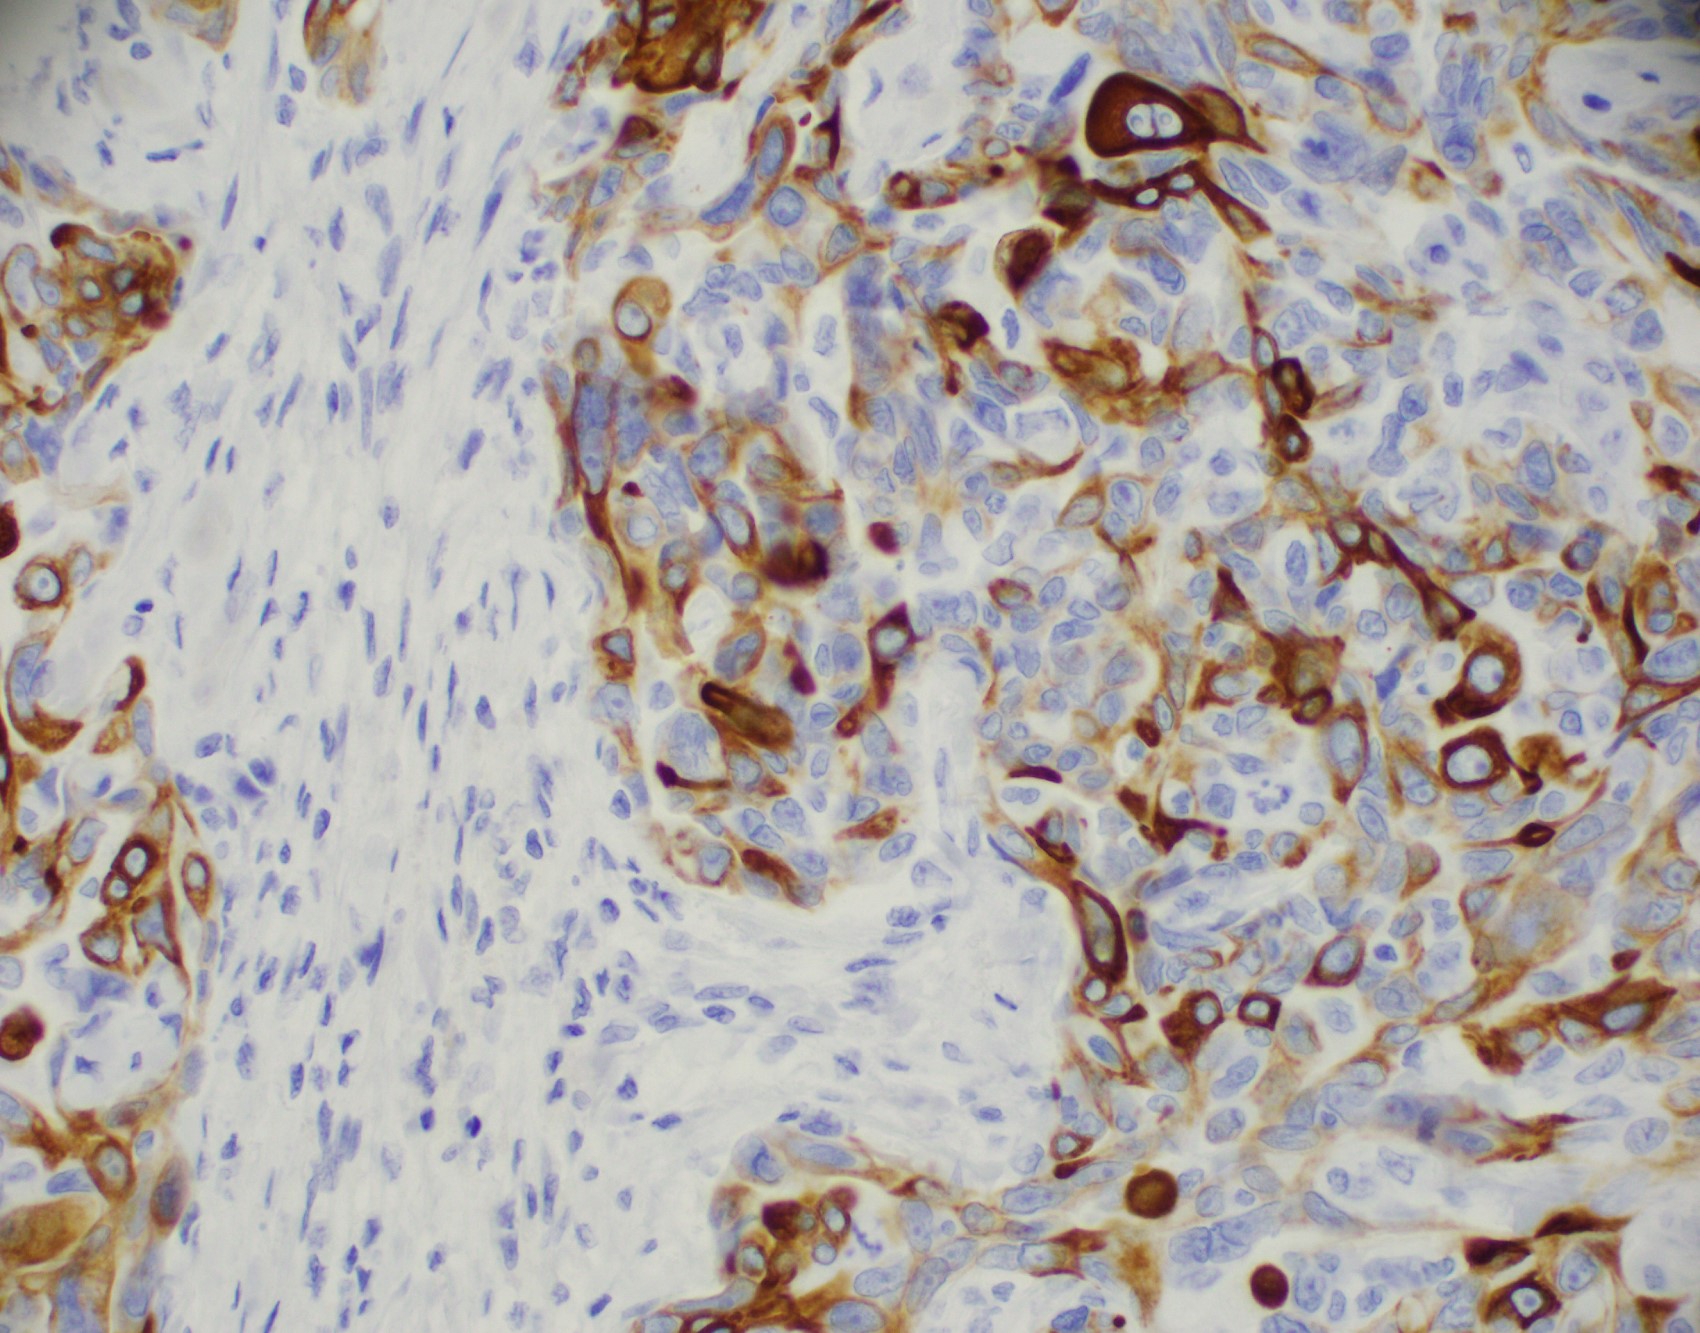

- No myoepithelial cell lining (as seen in DCIS or benign lesions)

- Angiolymphatic invasion in 35%; differs from tissue retraction because:

- Occurs outside margin of carcinoma

- Does not conform precisely to space it is in

- Endothelial lining is present and is CD31+, ERG, D2-40+, CD34+ and factor VIII+

Microscopic (histologic) images

Contributed by Julie M. Jorns, M.D., Kristen E. Muller, D.O., Gary Tozbikian, M.D. and Emad Rakha, M.D.

Positive stains

- Luminal low molecular weight cytokeratins (CK8 / 18, CK19 and CK7 and pancytokeratins such as AE1 / AE3, CAM 5.2, MNF-116), EMA, E-cadherin, p120, ER (60 - 80%), PR (50 - 70%), HER2 (15 - 20%) (Am J Clin Pathol 2006;125:377)